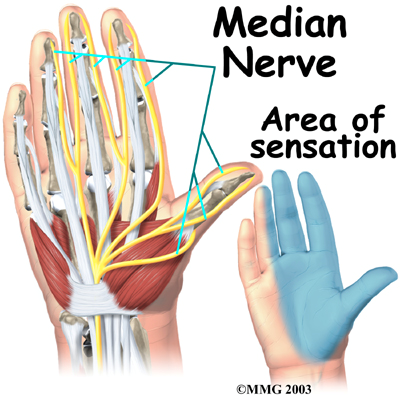

The median nerve (yellow-colored structure) passes through the tunnel and serves as the ‘communicator’, like an electrical wiring network, providing sensations to the thumb and nearby fingers (see photo about median nerve’s area of sensation). This nerve also controls the muscles in the palm, allowing them to move.

- Pain/ numbness/ tingling in the thumb, index finger, and middle finger (little finger or pinky usually not affected)